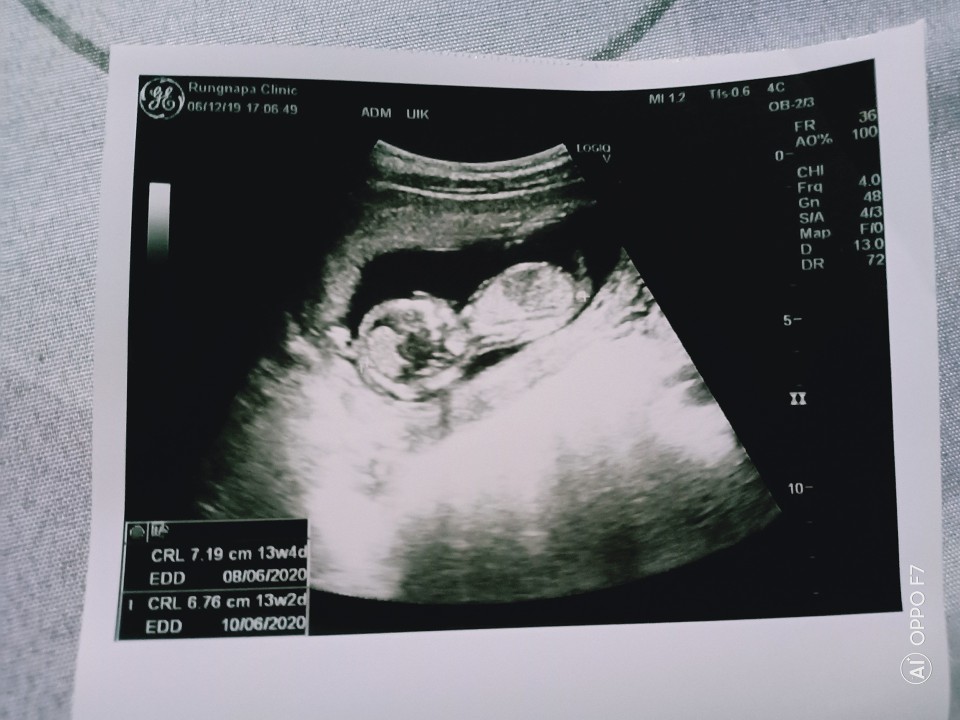

13w2d ค่ะ